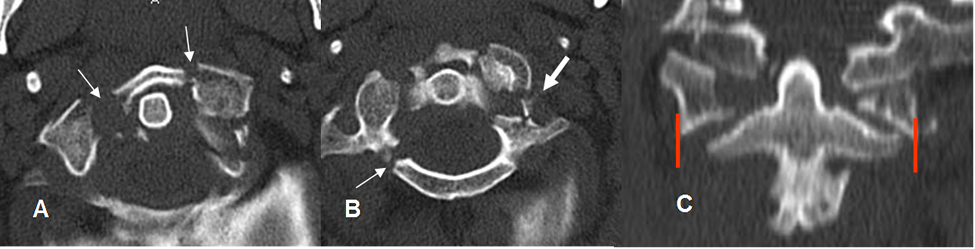

Fig 194. Fractura de C1.

A: Rx lateral. Alteración en la configuración de la articulación atlanto-axoidea.

B: TAC axial y C: TAC reconstrucción sagital. Fractura en el lado izquierdo, del arco anterior de C1.

Fig 195. Fractura de C1.

A y B: TAC axial. Fracturas aisladas y no desplazadas de C1. En A del arco anterior y en B del arco posterior.

Fig 196. Fractura de Jefferson.

A: Rx lateral y B: TAC reconstrucción sagital. Rectificación cervical, con aumento del espacio retrofaringeo.

El arco anterior de C1 está descendido, en relación con el borde superior de la odontoides, aunque se conserva el espacio normal.

Fig 197. Fractura de Jefferson. Igual paciente anterior.

A y B: TAC axial. Fractura conminuta del arco anterior y de la parte derecha del arco posterior. Existen fragmentos libres dentro del canal y compromiso del agujero vertebral en el lado izquierdo. (Flecha gruesa).

C: TAC reconstrucción coronal. Desalineación entre las masas laterales de C1 y C2.